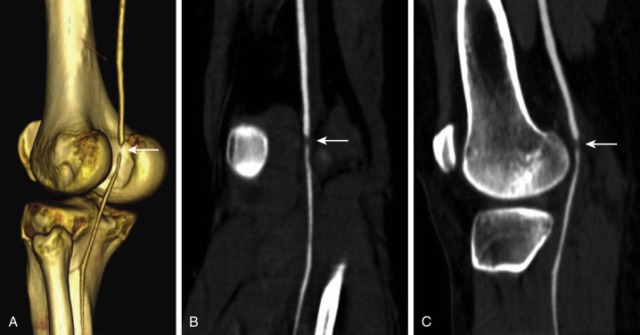

Diz BT taraması, diz bölgesindeki yapıları detaylı bir şekilde görüntüleyerek, çeşitli sağlık sorunlarının teşhisinde ve tedavisinde önemli bir rol oynar. Bu makalede, diz BT taramasının ne olduğu, nasıl yapıldığı, hangi durumlarda önerildiği ve sonuçların nasıl değerlendirildiği konularını ayrıntılı bir şekilde ele alacağız.

Diz BT taraması, bilgisayarlı tomografi (BT) teknolojisinin kullanılmasıyla diz bölgesindeki kemik, eklem ve yumuşak dokuların detaylı görüntülerini elde etmeyi amaçlar. Bu, çeşitli ortopedik ve reumatolojik sorunların teşhisinde yardımcı olur.

Diz BT taraması, kemik ve eklem sorunlarının teşhisinde kullanılır. Menisküs yırtıkları, kıkırdak hasarı gibi durumlar belirlenir.

Diz BT taraması, spor yaralanmaları, kaza sonrası yaralanmalar gibi durumların değerlendirilmesinde etkili bir araçtır.